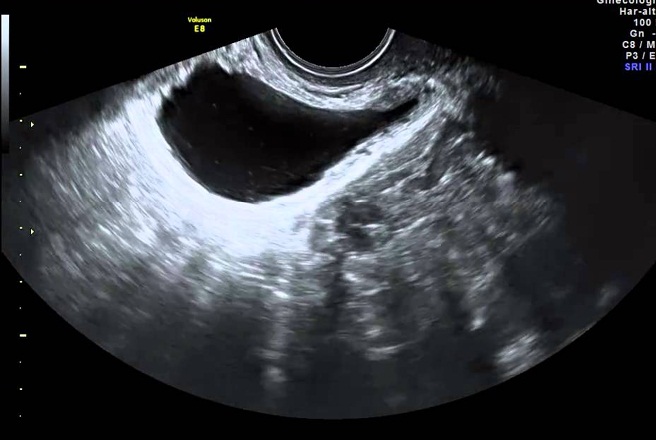

Así, líquidos como la orina, por ejemplo, aparecen como zonas no ecoicas atravesadas por ultrasonidos y por tanto negras en la pantalla, mientras que los tejidos ecogénicos, blandos o duros, devuelven imágenes más o menos claras según su composición.

- Vía intravaginal: una sonda cubierta con un condón recubierto con gel conductor se introduce en la vagina de la paciente acostada boca arriba, con las piernas dobladas;

El examen, indoloro, se realiza en un consultorio de radiología o ginecología, y generalmente dura menos de media hora. Existen dos técnicas de ecografía pélvica: la ecografía transcutánea, realizada a través de la pared abdominal; ultrasonido endocavitario, realizado en la vagina o en el recto.

Durante el examen, los ecos deultrasonidoson registradas por una computadora que las convierte en imágenes en movimiento, visibles en una pantalla. Luego, el médico registra las imágenes en las que desea medir ciertos parámetros (el crecimiento del feto y su desarrollo, el tamaño de un órgano, la presencia de una anomalía, por ejemplo).